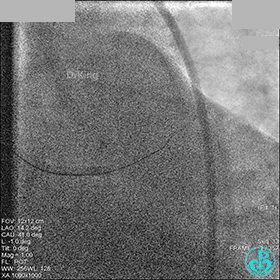

右冠脉血流3级,患者无症状,终止手术。

术后患者无特殊不适。

1周后再次上台,右冠脉3级血流,3段局限性严重狭窄,内膜模糊,应该是上次操作夹层遗留下的血肿。